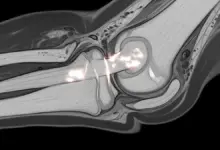

- Ressonância magnética: é o exame que mais ajuda no início, pois mostra edema ósseo, alterações subcondrais, extensão da lesão e sinais de risco de colapso.